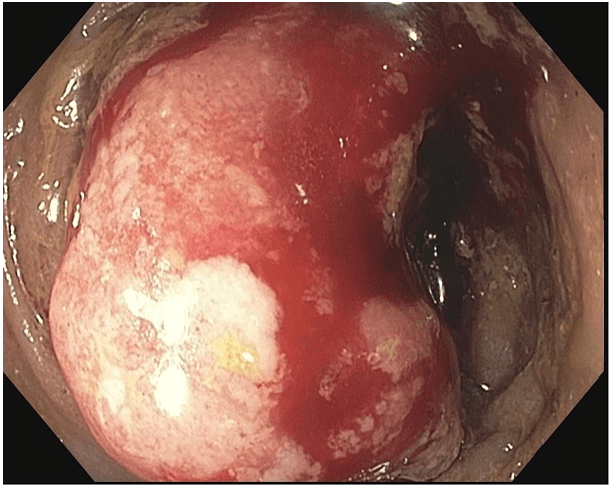

Figure 3. Endoscopic appearance of near circumferential, fungating and friable sigmoid mass.

A 67-year-old, morbidly obese female presented to the emergency department with a two-week history of fatigue and left-sided flank pain. Her medical history included breast cancer treated three years prior with chemoradiotherapy and radical mastectomy and chronic iron deficiency anemia. Her risk of developing colorectal cancer was considered that equal to the general population and she did not undergo routine screening. Patient was a non-toxic appearing, obese female with tender fluctuance along her left flank. Laboratory analysis showed microcytic anemia (hemoglobin-9.7 gm/mL, MCV-75), leukocytosis (total leukocyte count-14,800 cells/mm3), and acute kidney injury (creatinine 3.2 mg/dL, serum urea-88 mg/dL). Computed tomography without contrast showed a large subcutaneous air/fluid collection concerning for abscess along the left lateral abdominal wall with a fistulous communication to the sigmoid colon (Figure 1 and Figure 2). There were also inflammatory changes within the sigmoid colon with additional fistulas to the ileum and urinary bladder. The patient was started on intravenous fluids, antibiotics, and analgesics. Flexible sigmoidoscopy revealed a circumferential, obstructing, fungating, and friable sigmoid mass concerning for adenocarcinoma (Figure 3) which was confirmed by biopsy. Incision, drainage and washout of the flank abscess was performed for source control which yielded copious feculent material. Metastatic disease was absent on staging CT imaging thus surgical management with curative intent was pursued.